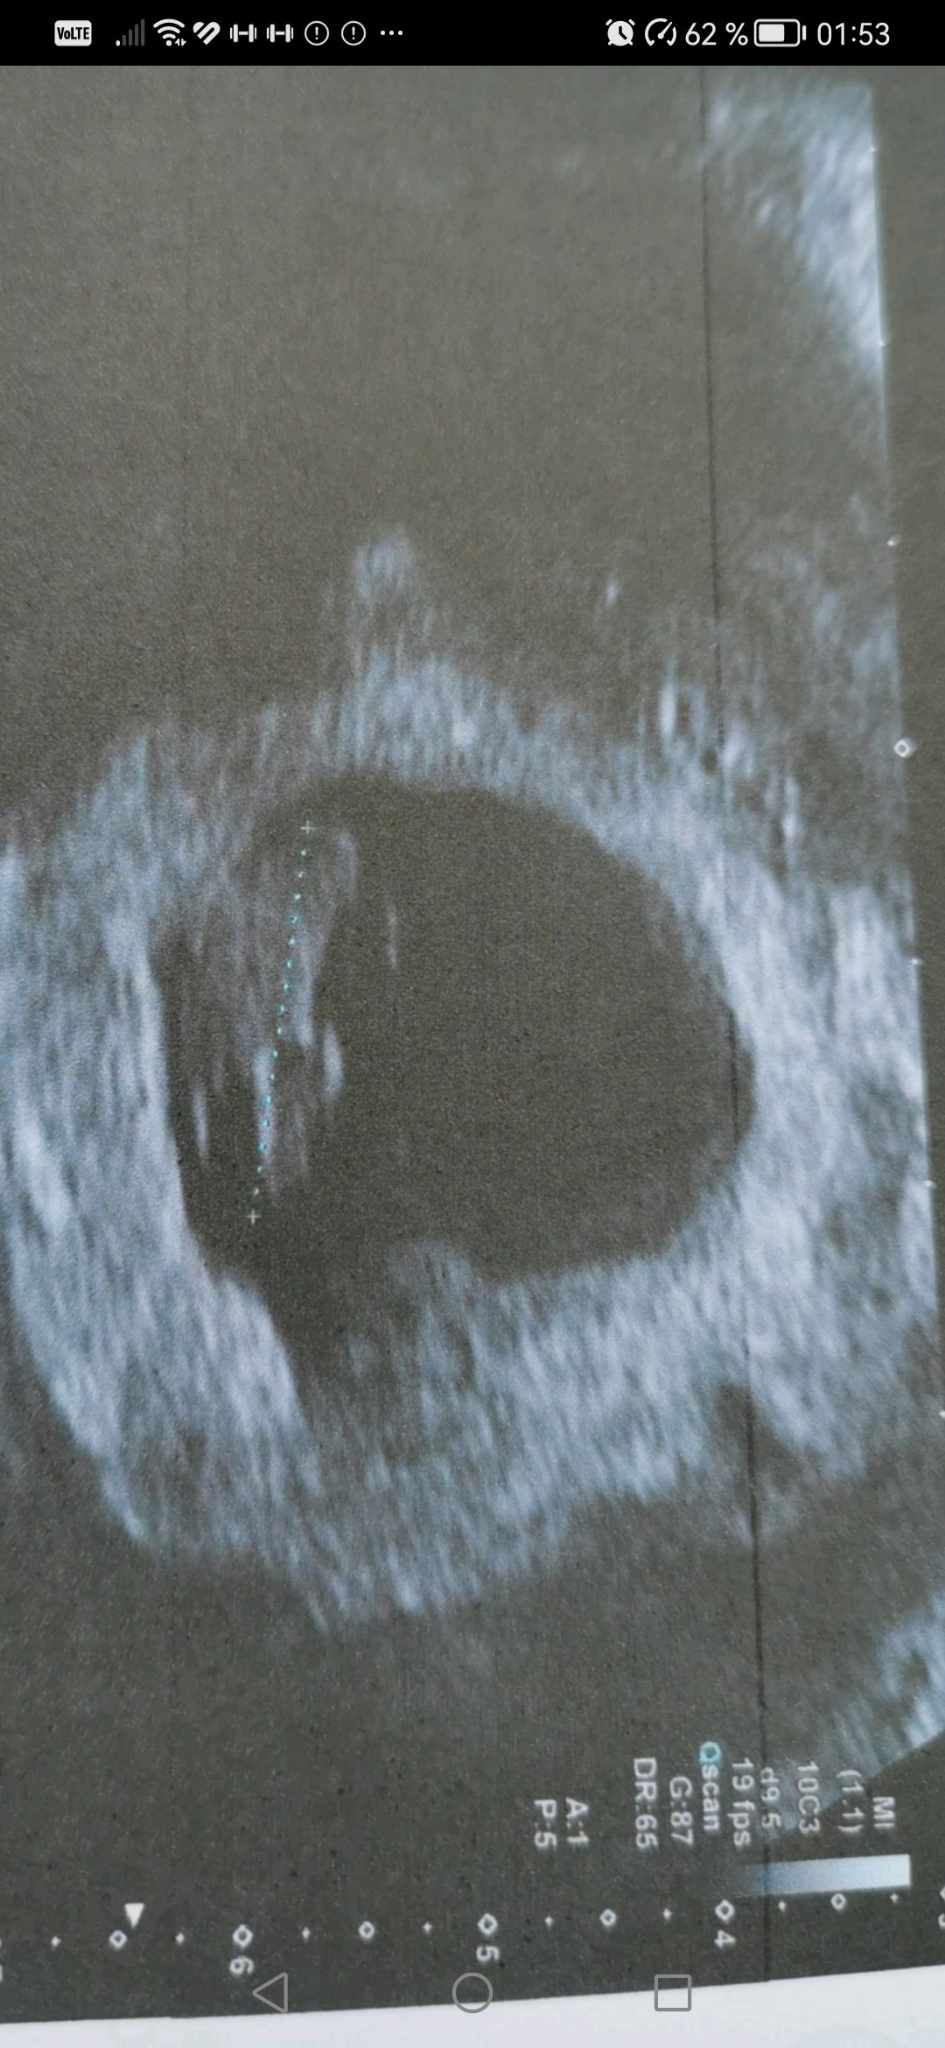

Mon écho s'est bien passée. J'ai frôlé la crise d'angoisse en salle d'attente...Tout va bien.

Son coeur bat : 162 battements / mn.

Il n'y a plus d'hématome. J'ai le feu vert de la clinique pour reprendre, dans un premier temps, l'aspégic un jour sur deux.

Je suis contente de voir une première photo de petit Pixel ! Vivement les prochaines !

Même si je ne fais que de petits passages furtifs, j'ai suivi avec plaisir l'évolution de tes taux, et le coeur bat de ton petit pixel, alors je t'envoie toutes mes félicitations !!!! Tu n'as rien lâché. Et bébé is coming ! Allez, on attend sagement les 3 mois.

Une image de plus dans l'album de Petit Pixel alorslasmoule a écrit : 24 févr. 2025 à 22:16Coucou,Elizabeth a écrit : 24 févr. 2025 à 17:45 Tellement contente pour toi Lasmoule! Quelle est la prochaine étape/écho ?

Visite cet après-midi: tout va bien. Nous sommes à 170 battements /min pour le coeur